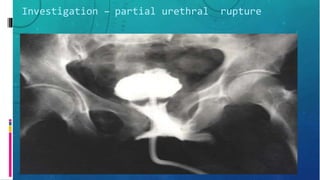

Investigation – partial urethral rupture

Investigation – partialurethral rupture

– Retrograde urethrography

• Confirms injury

• Location

• Severity

• Presence of foreign body

• Assoc injury e.g. Bladder